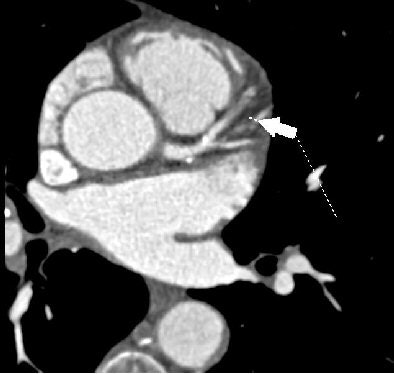

| All images were acquired in a 62-year-old man presenting to the hospital for evaluation of chest pain. CT-based assessment of cardiac function with akinesis of the anteroseptal wall, indicated by dark cold spectrum colors in an automatically generated functional model of the left ventricle. |